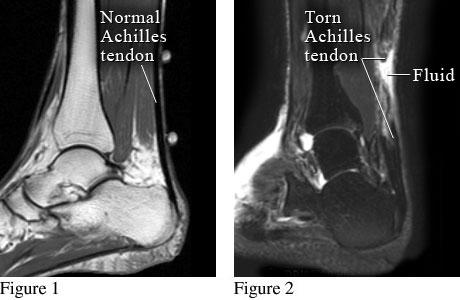

Normal Achilles tendon and torn Achilles tendon

Figure 1 shows magnetic resonance imaging (MRI) of a normal heel and Achilles tendon. Figure 2 shows a torn Achilles tendon with fluid collected at the site of the tear.